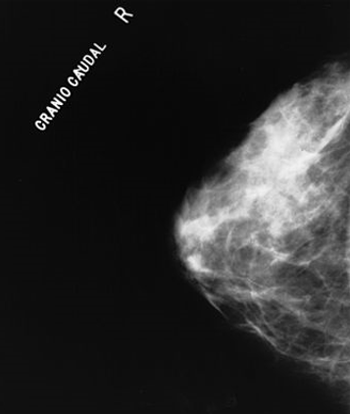

Adding molecular breast imaging to mammography resulted in a fourfold increase in invasive breast cancer detection rates in women with dense breasts.